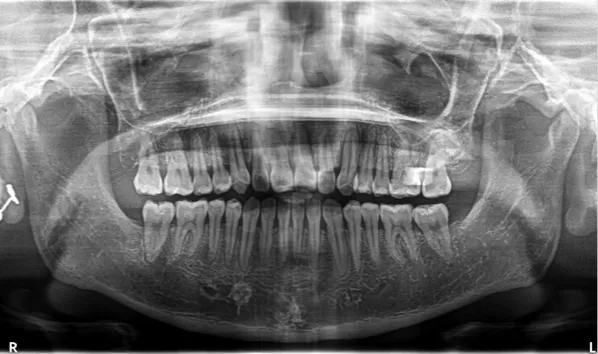

Rayons X après traitement

[Radiographie panoramique/Céphalogramme latéral]